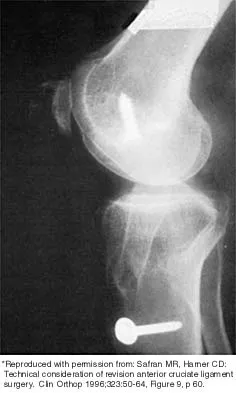

Figure 43 shows the lateral radiograph of a patient who underwent anterior cruciate ligament reconstruction. Based on the tunnel placement shown in the radiograph, evaluation of postoperative knee range of motion will most likely show

Explanation

The radiograph shows the correct tibial tunnel and anterior femoral tunnel; therefore, range of motion will most likely show loss of flexion. Brown CH Jr, Carson EW: Revision anterior cruciate ligament surgery. Clin Sports Med 1999;18:109-171.